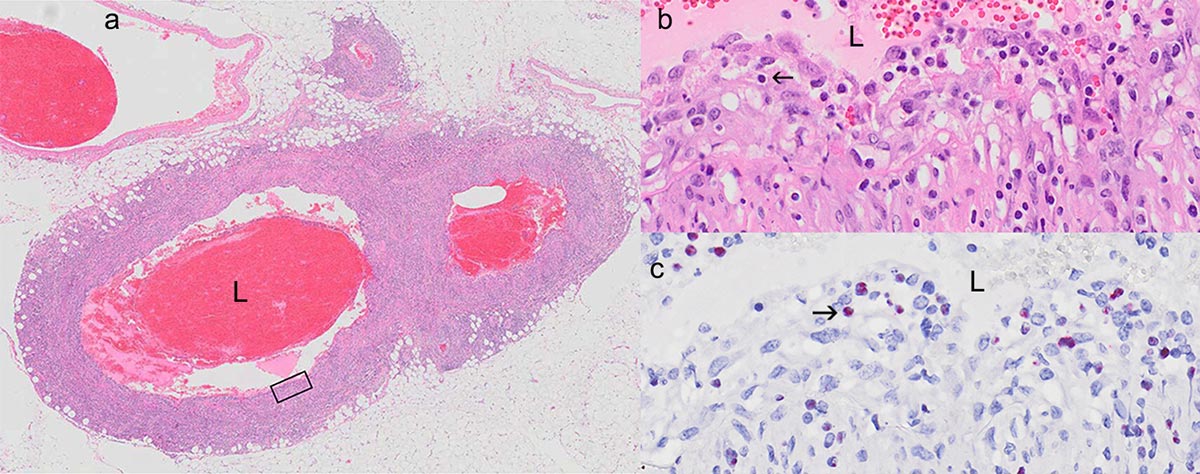

Figures 36 a-c In situ hybridization demonstration of OvHV-2 in tissues from an animal with acute MCF.

a. Artery with lymphocytic-histiocytic arteritis. L: arterial lumen.

b. Boxed area in a, showing lymphoid cells (arrow) in subendothelial and muscular layers in HE preparation

c. Infected lymphocytes (arrow) with red signal in ISH preparation.

(Courtesy of P Pesavento, UC Davis, California, USA)

A strong tentative diagnosis of MCF can be made based on clinical signs in consort with typical gross and histological lesions of MCF. A small fraction of cattle dying of MCF will have lesions that are equivocal for diagnostic purposes. Such doubtful cases can be resolved by PCR.135 Confirmation involves nested or quantitative PCR assays.74,118,135,207,217 Correlation between lesions suggestive of MCF and a positive PCR result is generally excellent. If an outbreak involves an MCFV other than OvHV-2 or AlHV-1, a multiplex PCR is available.39 At present there is no immunohistochemical method to confirm a diagnosis of MCF in formalin-fixed tissues, presumably because scant viral antigen is expressed in end-stage hosts. Provided formalin fixation of tissue is not prolonged (<45 days), wax-embedded tissue can be tested by PCR to corroborate a clinical or morphological diagnosis when fresh tissue is unavailable. Fixed tissues stored in wax blocks for up to 15 years have been tested successfully, and provide a useful resource for retrospective studies34,64,145 and in situations where no fresh tissues were collected.193 In situ hybridization methods (Figures 36 a-c) can demonstrate AlHV-1 and OvHV-2 in fixed tissue, but are rarely used diagnostically.123,152,153 It has been helpful in establishing the presence and probable involvement of OvHV-2 in natural outbreaks of systemic polyarteritis in sheep.153